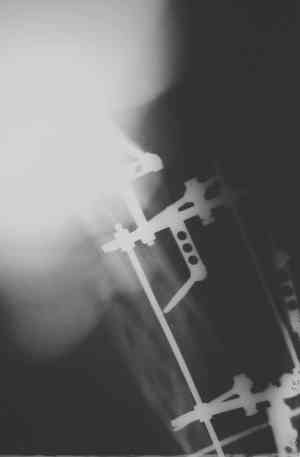

Уважаемые коллеги! Пришел на консультацию вот такой больной (первые 3-и рисунка). Травма автодорожная, апрель 2006г. Лечился консервативно, вытяжение и гипс. Через пять месяцев стал ходить. Укорочение бедра 6 см. 26 февраля 2007г. оступился, упал. Прооперирован в г.Баку - наложен стержневой аппарат. Ходит с костылями, наступая на левую ногу.

Мы попросили что нибудь из ранних снимков. Принес рентгенограммы перелома (рис. 4,5). Посмотрели, наснимали сами (рис. 6-10). Похоже, что нет сращения нигде. Хотелось - бы обсудить следующие вопросы: 1. дальнейшая тактика - реостеосинтез или подождать (ослабить аппарат, дать нагрузку и т.д.)? 2. если реостеосинтез - то чем и как? Юрий Алексеевич Булахтин